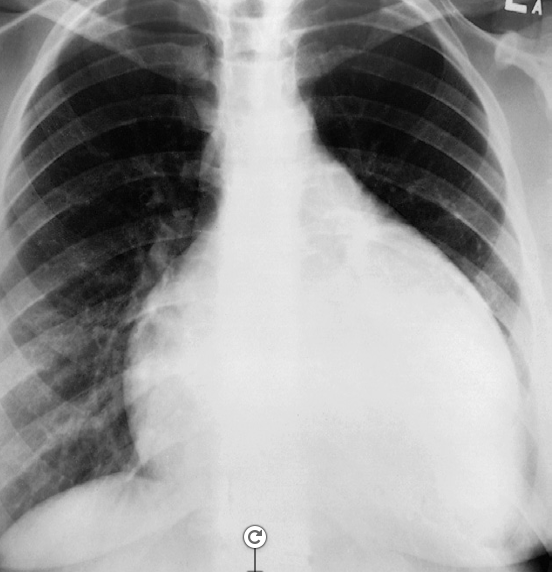

Congestive cardiac failure. There are large bilateral pleural effusions. The heart is enlarged although it is difficult to measure it precisely because the pleural fluid obscures its borders. //– Chest x-ray pleural effusion both, in right costrophrenic & left meniscus sign -